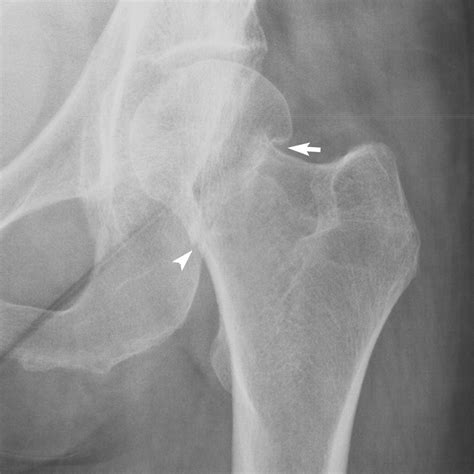

The impaction of fracture occurs when a bone sustains a high-energy impact that forces the fragments together, effectively "wedging" the bone tissue into itself. Unlike a transverse or oblique fracture where there is a clear break and separation, the impacted bone remains locked in a collapsed position. This is frequently seen in regions of the body characterized by cancellous (spongy) bone, such as the neck of the femur, the proximal humerus, or the wrist (distal radius).

Because the bone fragments are locked together, they may appear deceptively stable on initial physical examination. However, this inherent stability does not negate the severity of the trauma. The impaction often leads to shortening of the bone, alteration of joint mechanics, and potential damage to the surrounding blood supply, which is particularly critical in areas like the femoral neck.

• Femoral Neck: Often resulting from falls, these are critical due to the risk of avascular necrosis.

Diagnosing the impaction of fracture requires high-resolution imaging. A standard X-ray is the first line of defense, but it can occasionally miss the subtlety of the impaction if the viewing angle is not optimal. Orthopedic surgeons rely on specific radiographic views to identify the degree of angulation and the extent of bone compression.